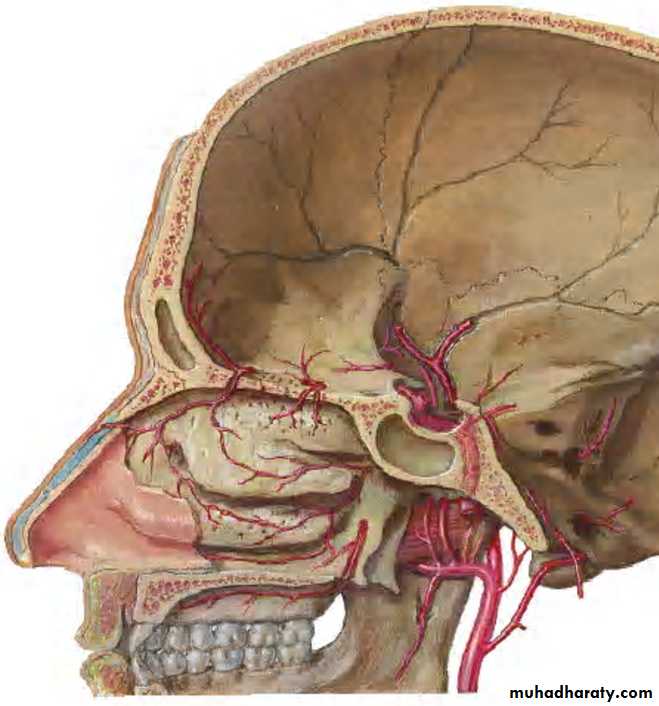

BLOOD SUPPLY:

ARTERIAL:By facial artery branch of ECA.

By infra orbital & greater palatine arteries branch of max. art which is branch of ECA.

VENOUS:

To anterior facial vein& pterygoid plexus.

NEUROVASCULAR SUPPLY:

Blood supply - Supra orbital arteryVenous return - Anastomotic veins in supra orbital notch, connecting supra orbital and supra ophthalmic veins.

Blood supply:Posterior ethmoidal artery

Venous drainage:

Pterygoid plexuses

Arterial supplyAnterior ethmoidal artery(ophthalmic artery)

Post. Ethmoidal artery

Sphenoidal artery(maxillary artery)

Venous drainage

Ant. Ethmoidal vein

Post. Ethmoidal vein